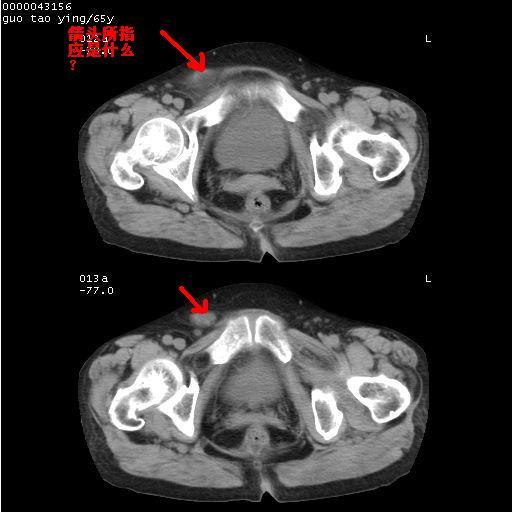

以下是引用黑白光影在2008-1-30 13:22:00的发言:[br]支持左耻骨骨折。[br]未见骶骨骨质明确破坏改变。[br]经楼主提示(勿局限于外伤)。考虑为右侧腹股沟直疝。[br][br][br][br]